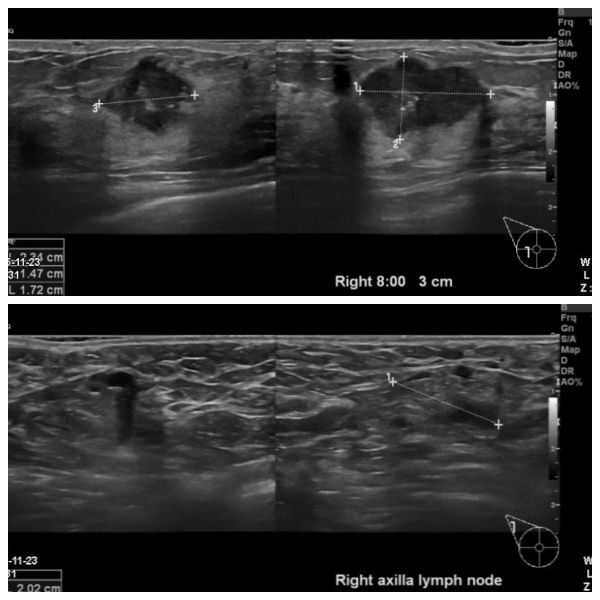

우측유방에 만져지는 멍우리로 내원하신 50대 환자분이십니다.

본원에서 우측8시 방향에 혹과 겨드랑이림프절을 각각 조직검사,세침검사 시행하였고

결과상 침윤성 유관암 진단되었고 겨드랑이 전이까지 확인되었습니다.